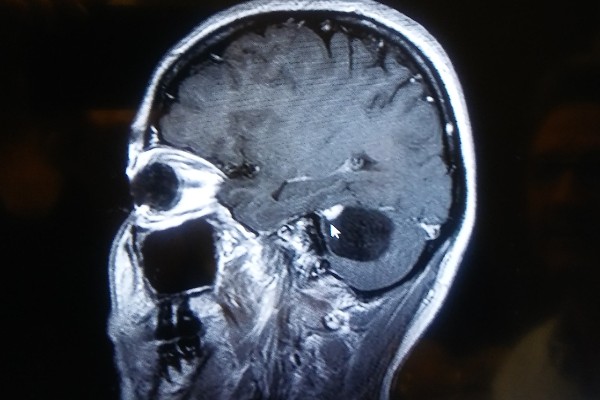

I went to a Neurologist because I became very dizzy all the time, and couldn't really function well with my right hand. Simple things like writing and typing (even my eyeliner!) have become difficult. After an MRI, the Neurologist showed me that I have a brain tumor that needs surgery. At the same time, I am taking care of my mother who several specialists for her mental and physical problems. I take her to all (a lot) of her appointments, manage her medications, and instill her Glaucoma drops. I am busy at work, and am actually about to train someone. Needless to say, I just don't have time for this, but things don't always happen when it's convenient! I have tried to find an insurance plan or Obamacare to cover this, however I couldn't find anything to help for 2017. The Neurosurgeon said that the surgery doesn't need to be postponed until January 1st due to the complications that may arrise. If the spinal fluid backs up, I only have a short time before it becomes fatal. I have to pay for the Neurosurgeon before they will schedule a date to do surgery for me. I love that I got prayers and links for different organizations from you, and I am doing what I can with them, but it was suggested by some friends and family that I try a Go Fund Me. I am doing this myself, since I wanted to tell you about things first hand. I am told I will probably be unable to work for approximately 6 weeks. This Go Fund Me will help tremendously.